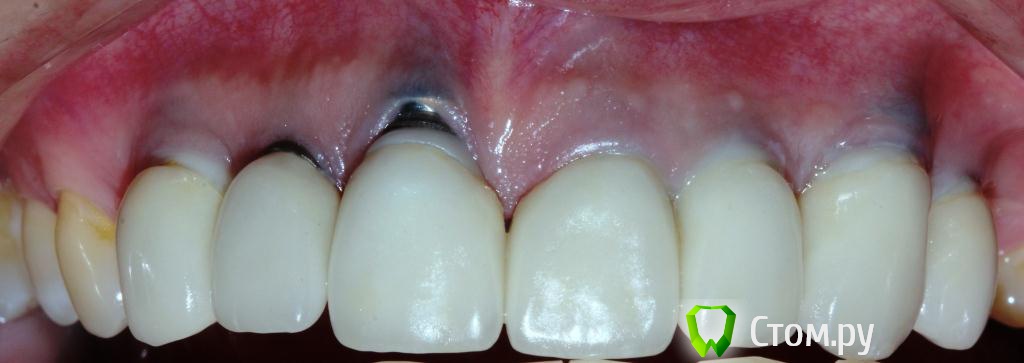

zzkz Опубликовано 27 ноября, 2014 Поделиться Опубликовано 27 ноября, 2014 2 года назад установили имплантаты, ДЦ абатменты и коронки. На сегодня такая ситуация. Имплантаты интегрированы.+ ко всему форма зубов не устраивает(крупные). Налета на фронтальных нет вообще(пользуется ирригатором только во фронте), на нижних дистальных околопришеечный налет и в области них совсем нет ЗКПД. Какая система имплантатов она не знает. Если придется снимать коронки, что посоветуете. Какой набор может универсальный приобрести? Насколько реально закрыть рецессии? В какой последовательности лучше идти? 1 Ссылка на комментарий

Den5 Опубликовано 27 ноября, 2014 Поделиться Опубликовано 27 ноября, 2014 Плюсую за попытку попробовать мягкотканноСработает тоннель+ССТ,только там где не оголены импланты Ссылка на комментарий

ILGAMSA Опубликовано 27 ноября, 2014 Поделиться Опубликовано 27 ноября, 2014 Какие торки на астре? Стоит ли для этого снимать всю конструкцию или так же как при рецессии на зубах? Как думаете по поводу нижних. Там уже перимукозит. Есть легкая кровоточивость. Лучше снять.Перимукозит обратим.Торки 3,0 - 153,5/4,0 - 204,5 - 25 2 Ссылка на комментарий

Bier Опубликовано 27 ноября, 2014 Поделиться Опубликовано 27 ноября, 2014 Я бы 6 раз подумал прежде чем браться... Но согласен, что только мягкими тканями можно выводить 1 Ссылка на комментарий